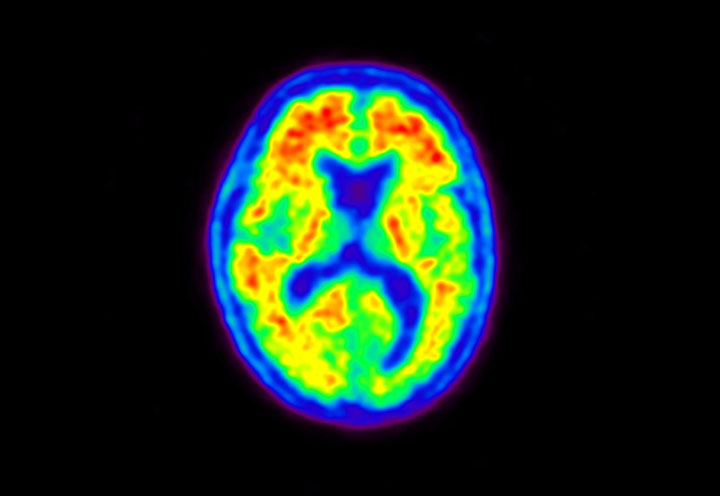

Head / Case5 : Amyloid

Axial

Courtesy : Kindai University Hospital

- Imaging protocol

- Injected dose: 4.27 MBq/kg, 18F-Flutemetamol

- Uptake time: 99 minutes

- Scan time: 20 minutes